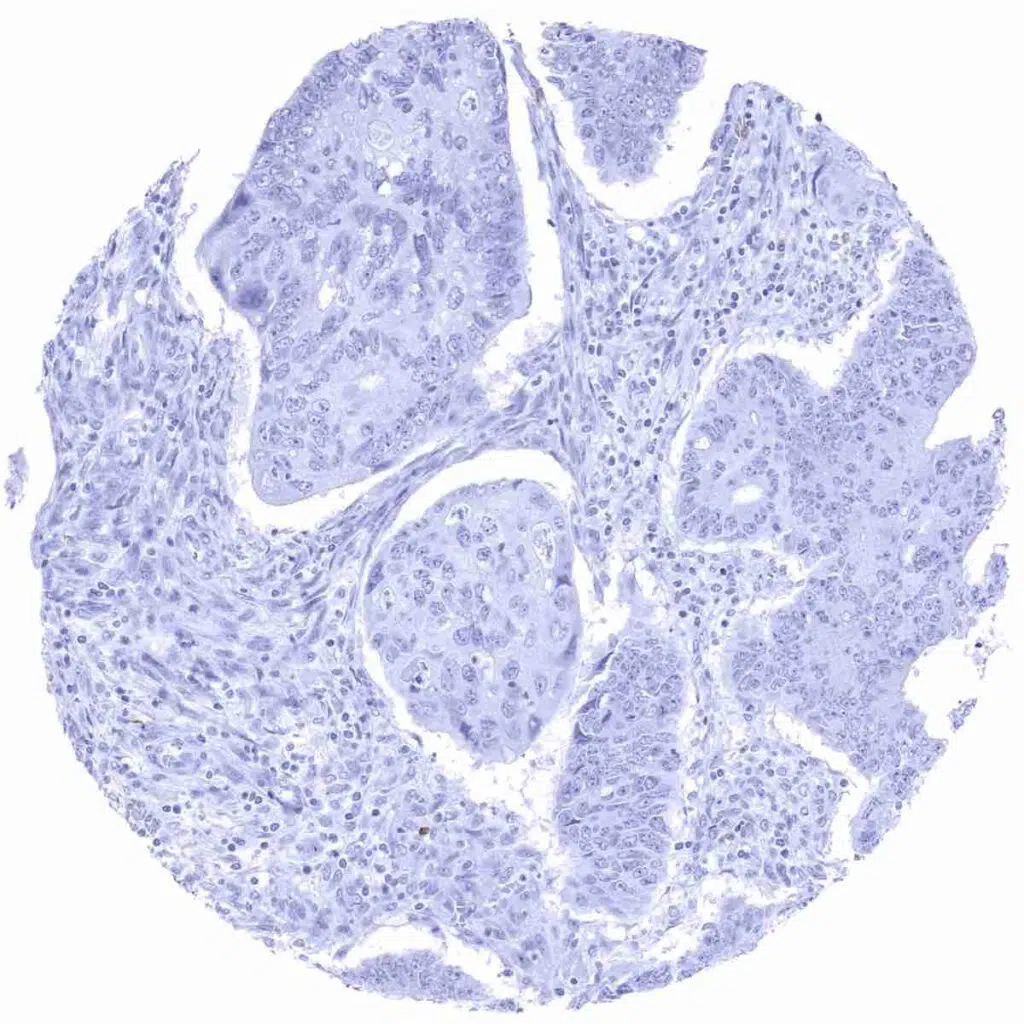

CD22 antibody [MSVA-022R] HistoMAX

Prostate- Adenocarcinoma (Gleason 3+3=6) containing multiple CD22 positive lymphocytes